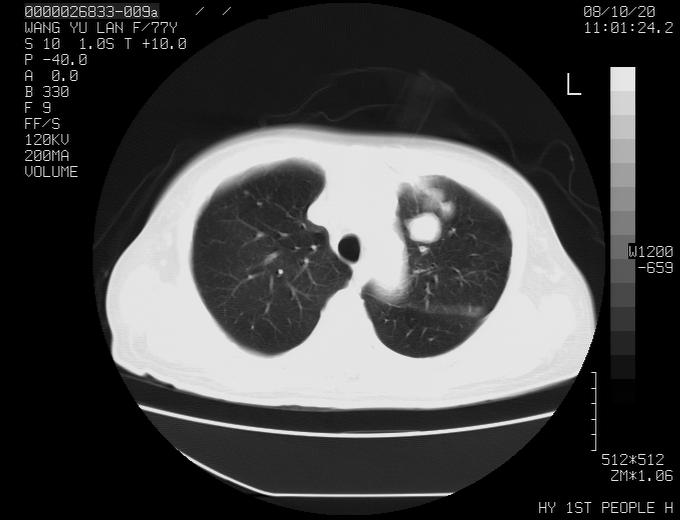

女性,77岁,胸部疼痛半月。左上肺团块影,本人考虑血管畸形,请分析

左上叶前段多发结节肿块并前段支气管息肉样结节、上叶腋亚段阻塞性肺炎,以结核可能性大。

纵隔有多个淋巴结肿大,提示周围型肺癌并转移可能性大。

动脉期未见大血管同步强化,首先考虑周围型肺癌

动脉期病灶近中线侧可见星芒状与大血管同等强化密度,支持考虑血管畸形伴血栓形成,动脉期不曲型,不除外周围型肺癌

1、考虑avm可能性大。2、纵隔有肿大淋巴结,左肺上叶有炎性病变,不排除肺癌并转移可能。